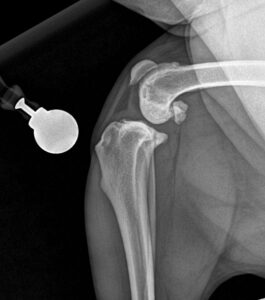

• TPLO Surgery for Cruciate Damage & Other Orthopaedic Surgery

TPLO pre op